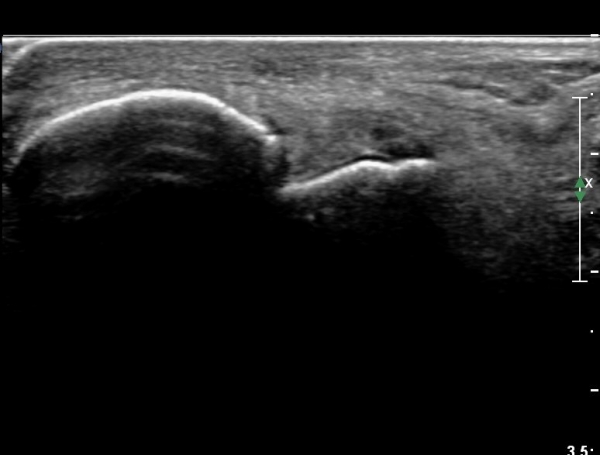

Àü°ÅºñÀÎ´ë ºÎÇϰ˻翡¼­ ÀδëÆÄ¿­ ºÎÀ§°¡ ¹ú¾îÁö°í °Å°ñÀÌ ¾ÕÀ¸·Î ´Ü°ÜÁö´Â ¼Ò°ßÀ» º¸ÀÓ(»çÁø 3, 4, ÷ºÎ µ¿¿µ»ó).